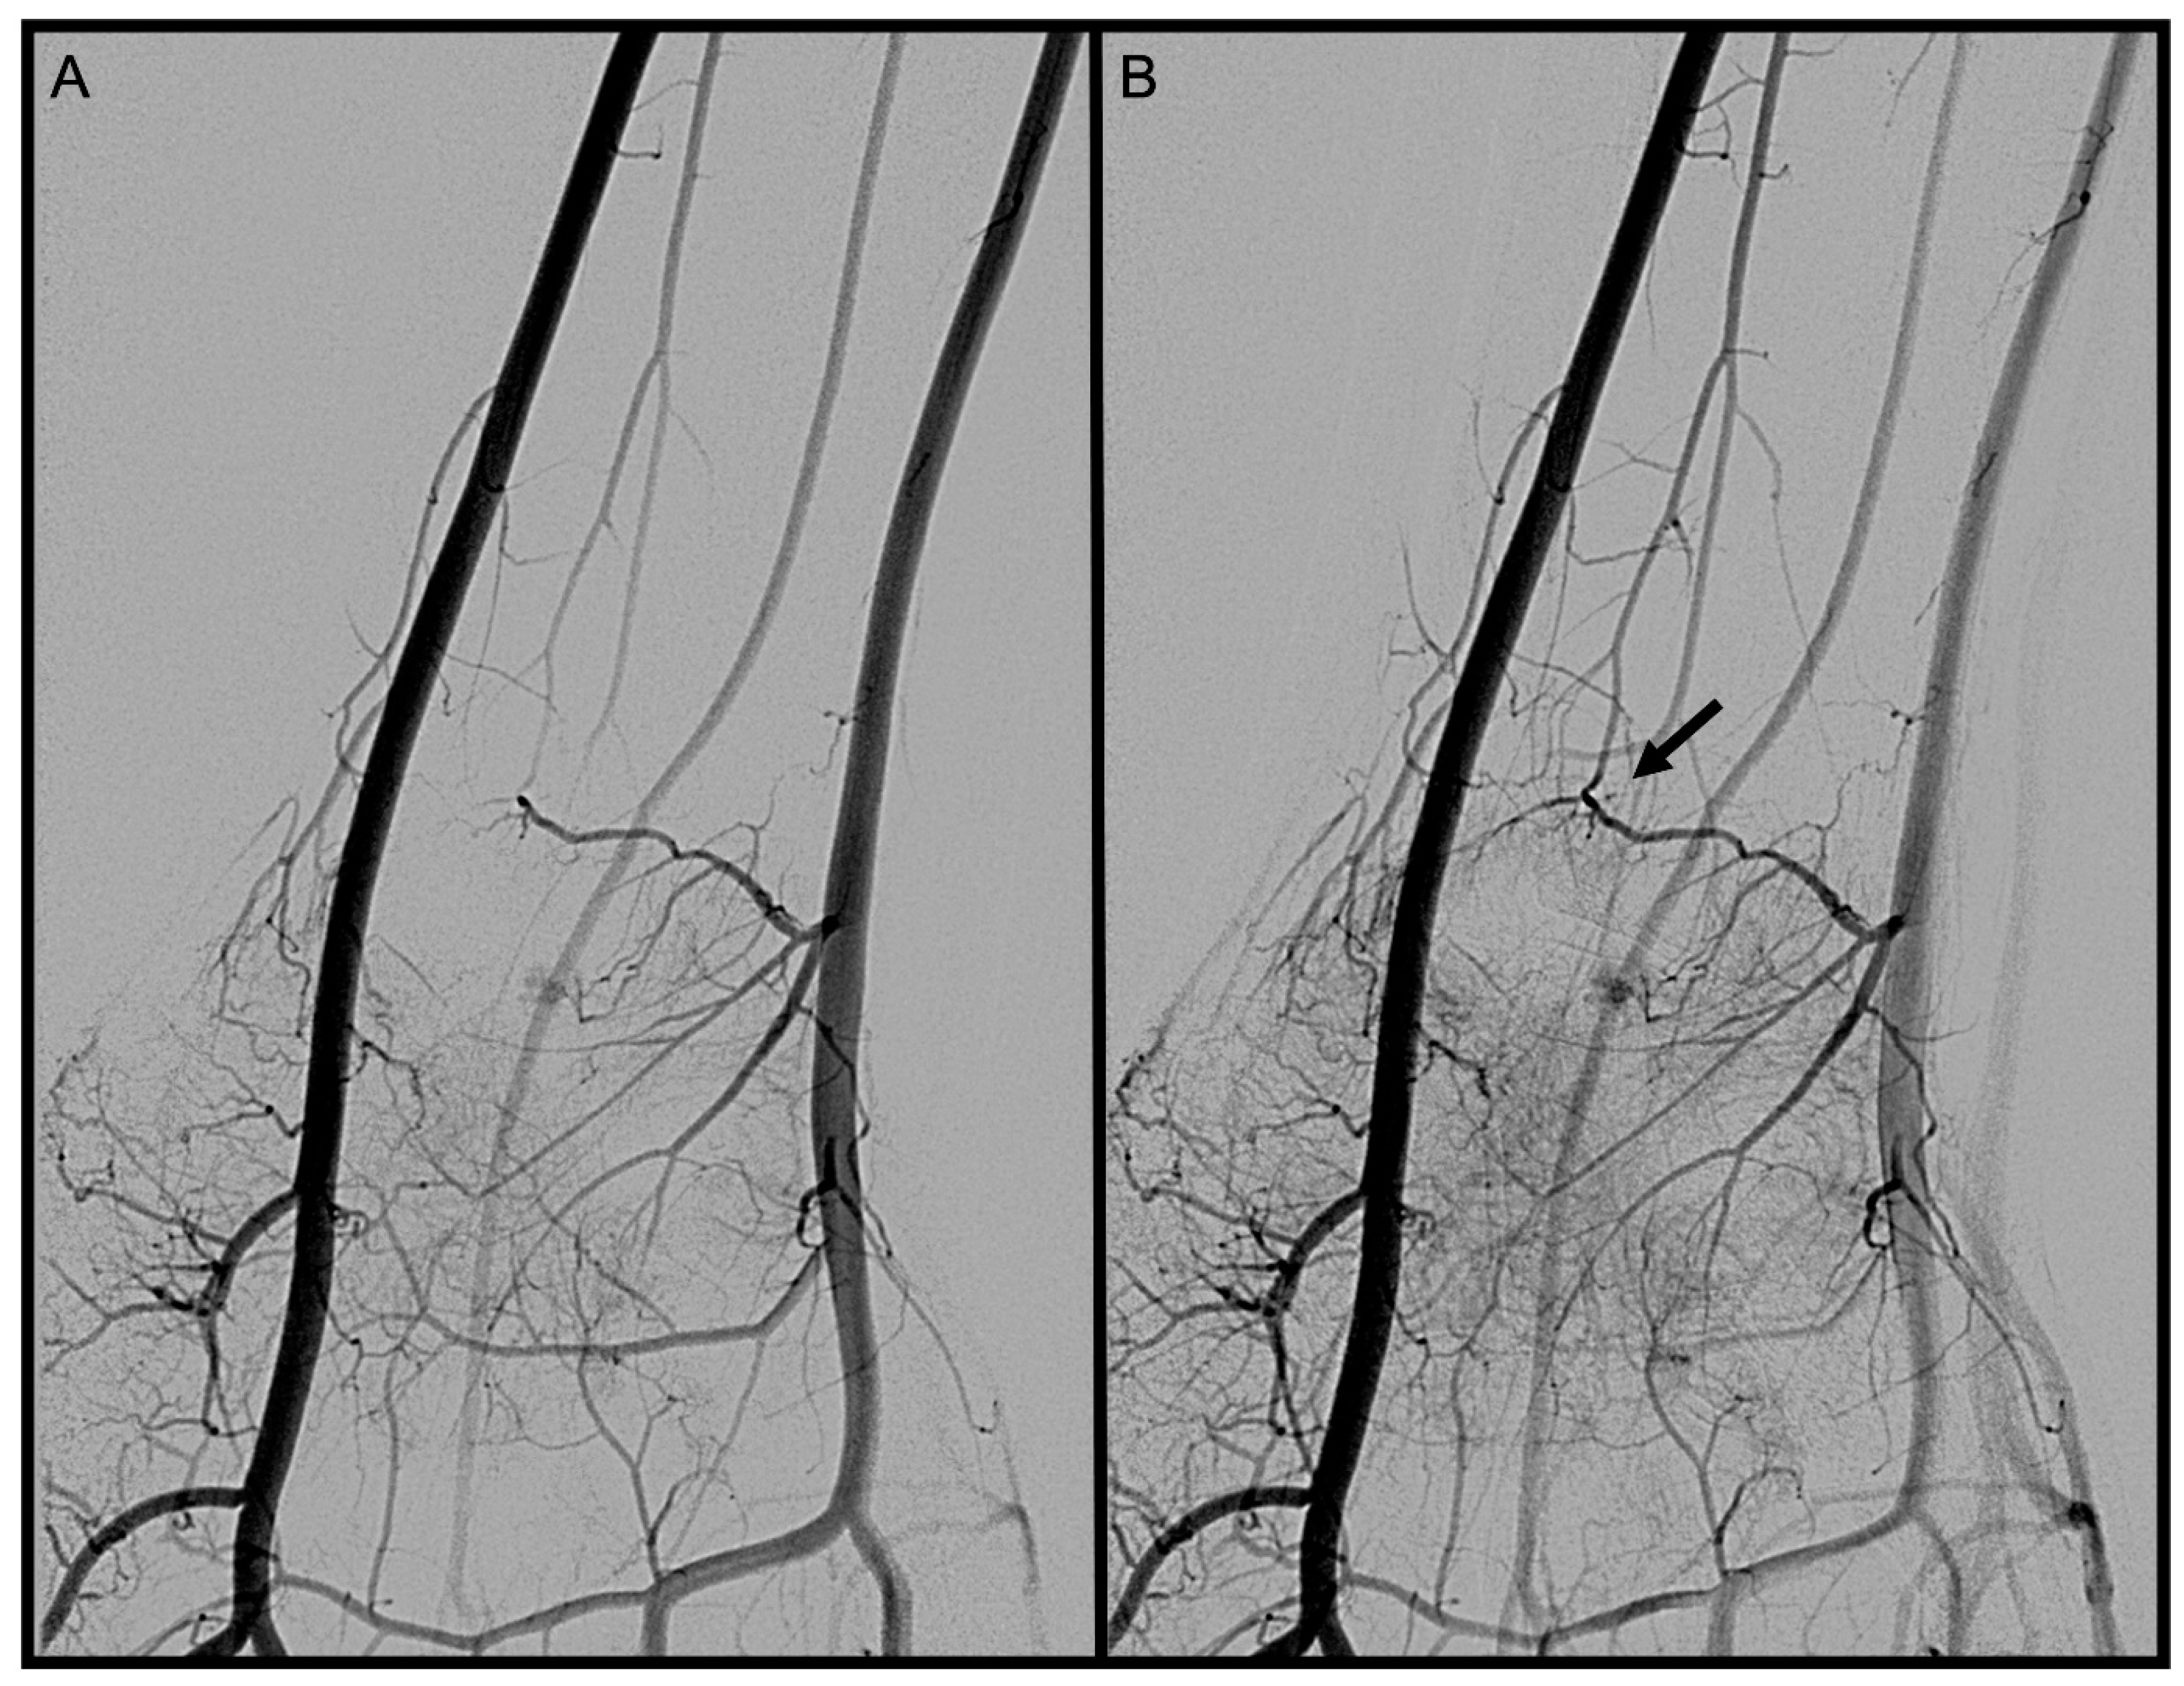

3.1. Palmar Radiocarpal Artery and Palmar Radiocarpal Arch (PRCA)

3.2. Dorsal Carpal Branch of the Ulnar Artery (DCBUA)